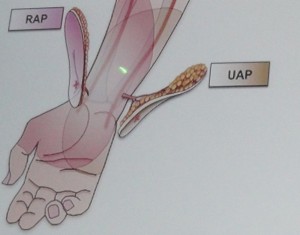

За период с 2008 по 2011 в клинике с целью закрытия дефектов кожи и мягких тканей на конечностях и туловище прооперированы 12 пациентов, у которых выполнено: пять кожно-фасциальных пропеллер лоскутов (PPPF) на перфоранте из басейна локтевой артерии (UAP), два торакодорзальных лоскута с транспозицией по типу пропеллера (TDAP), один лоскут (PPPF) на базе перфорантной артерии из басейна задней большеберцовой артерии (PTAP), четыре латеральных надлодыжечных лоскута на перфорантной кожной ветви малоберцовой артерии (PNAP). Параметры лоскутов представлены в таблице 1.

В клинике проведена диагностика повреждения. Определена зона иссечения патологических грануляций, выполнена обработка торцов метакарпальных костей, лоцированы перфорантные сосуды – UAP (Рис. 6А), намечен дизайн кожно-фасциального перфорантного пропеллер лоскута, размерами 15 х 4 см, который после диссекции и визуализации сосудов питающей ножки ротирован аксилярно на 180 град., адаптирован на подготовленном раневом реципиентном ложе. Рана закрыта полностью без натяжения тканей. Донорская зона закрыта путем наложения линейного шва. Послеоперационное течение без особенностей. Пациент выписан на 25 сутки после поступления.

Фото. 6. А – варианты формирования островковых лоскутов пропеллер на питающей ножке, состоящей из выделенных изолированных перфорантных сосудов (perforator pedicle propeller flap – PPPF) из бассейнов лучевой (RAP)и локтевой артерий (UAP) для пластики дефектов кожи и мягких тканей в области кисти. Б – цифровое фото перемещенного на рану культи кисти островкового кожно-фасциального пропеллер лоскута (PPPF) на перфоранте из басейна локтевой артерии. В,Г – результат демонстрирует восстановленную функцию захвата кисти в области первого межпальцевого промежутка.